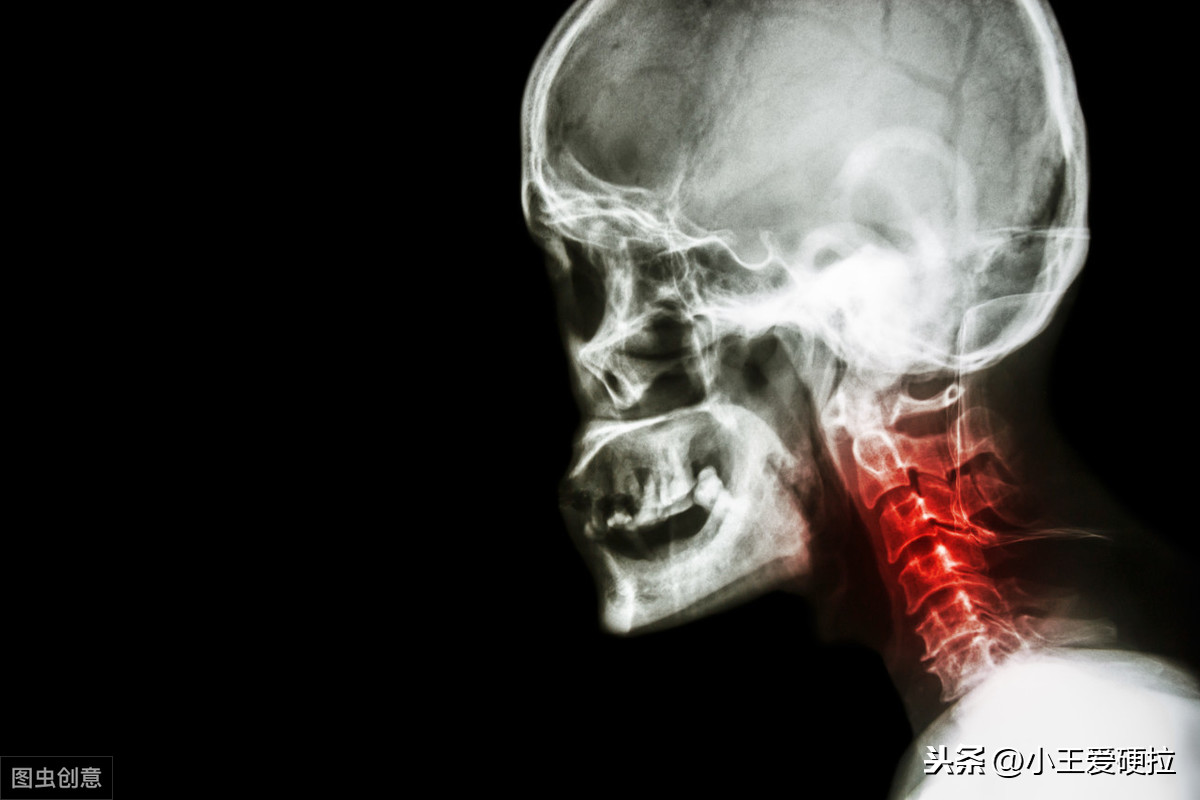

本文将会介绍 1,颈椎病的凶手和受害者。 2,肌肉软组织的拉伸与手法松解技术(恢复灵活性)。 3,形成颈椎病的各种原因及针对性解决方法。 4,重建颈椎稳定性(肌力训练) 5,颈椎病改善策略 “凶手”和“受害者”面对身体疼痛或者其他不适,我们要先搞清楚“凶手”与“受害者”之间的关系,才能从根本上解决或者改善问题。 比如说,头疼可能是因为供血不足,或者是颈肩肌筋膜软组织紧张形成的牵涉痛,那么供血系统和肌筋膜软组织就是造成疼痛的“凶手”吗?实际上并非如此!

我们需要继续思索是什么原因造成了供血不足和软组织紧张----答案就是我们的不良工作生活习惯。(比如呼吸模式紊乱,比如低头看手机,比如电脑前的久坐,比如过高的枕头和奇怪的睡眠姿势) 除了某些外伤因素,一个人患上颈椎病的顺序大致是这样的:糟糕的生活习惯习惯先使头颈部支撑结构被动失衡,软组织张力增加出现劳损,慢慢颈椎生理曲度改变,出现间盘突出、间隙变小,骨刺骨赘韧带肥厚等退行性病变,然后刺激或压迫脊髓、神经根、椎动脉等组织,最终导致出现眩晕、麻木等一些列颈椎病症状。 眩晕或疼痛=症状;肌筋膜=受害者;生理结构改变=受害者;糟糕的生活工作习惯=凶手! 面对身体的不适,我们需要的是解决“凶手”,而不是一味地安抚“受害者”。而解决问题的步骤,应该是先安抚受害者(急性期的休息、消炎、针灸、按摩等),然后再抓住凶手(改变糟糕的生活工作习惯+纠正不良体态)。